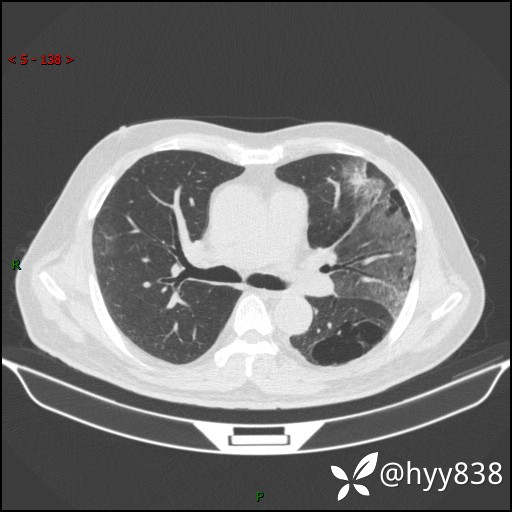

一周后胸部CT